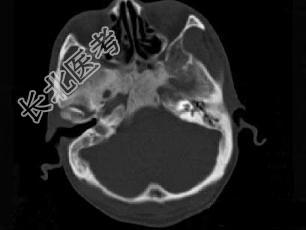

- 单项选择题男性,56岁, 鼻咽癌放疗后复查,CT扫描如图所示, 请选择正确的答案 ( )

D、放疗后骨炎